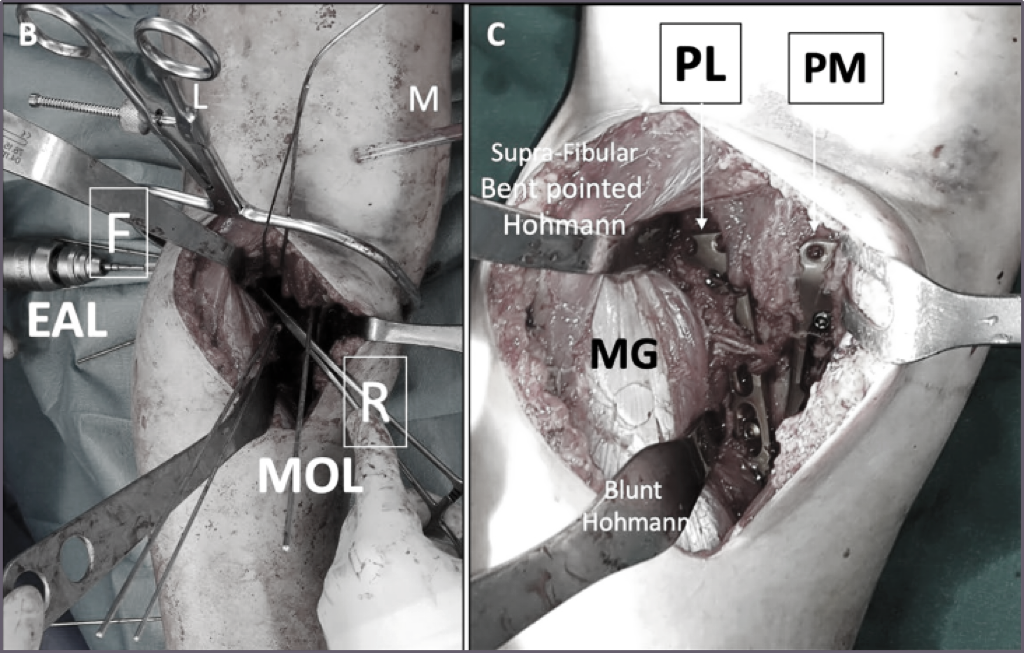

B,在MOL入路的直接观察下,使用90°解剖钳将PL柱碎片复位(R)。同时,通过EAL入路(腓骨前窗)对关节PL碎片进行临时和确定性固定(F)。还请注意,在此位置同时复位并临时固定后内侧和外侧柱。

C,最终复位后外侧皮质并用后外侧(PL)板固定。后内侧(PM)板处于适当位置以抵消PM-MDD。注意胫骨平台外侧腓骨头上方近端弯尖Hohmann牵开器的位置。在此图中,远端钝Hohmann靠在PL板上以放松张力。